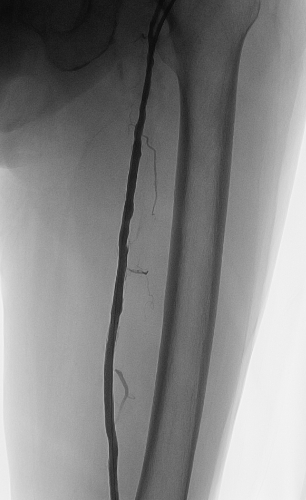

术中李龙虎主任结合造影结果,实施了手术:开通左股浅动脉改善大腿血流,开通左胫前动脉改善小腿及足部血流。送入JR4.0 导引导管,泥鳅导丝多次尝试下可通过股浅动脉远段闭塞病变并送至胫前动脉闭塞病变前,交换V18导丝,先以5.0*150mm外周PTA Catheter扩张股浅动脉中远段病变(图3),复查造影见股浅动脉中远段病变残余狭窄明显改善,再多次尝试下V18导丝可通过胫前动脉闭塞病变至其远段,再送入3.0*150mm外周PTA Catheter由远及近预扩张胫前动脉(图4),复查造影示胫前动脉残余狭窄改善,再送2.530mm药物洗脱外周球囊至胫前动脉扩张释放药物(6atm180s), 复查造影示胫前动脉无明显残余狭窄(图5),血管无穿孔、夹层,远段血运良好。再送5.0*150mm外周PTA Catheter充分扩张股浅动脉中远段病变,再于股浅动脉中远段病变由远及近串联植入支架,复查造影示支架贴壁良好(图6),血管无穿孔、夹层,远段血运良好。术毕,退出鞘管,以血管缝合器缝合穿刺口,无菌方纱包扎,安返病房,术程顺利,病人无不适。术后左下肢足背动脉搏动良好,左下肢疼痛消失,无间歇性跛行。

图4 胫前动脉球囊扩张